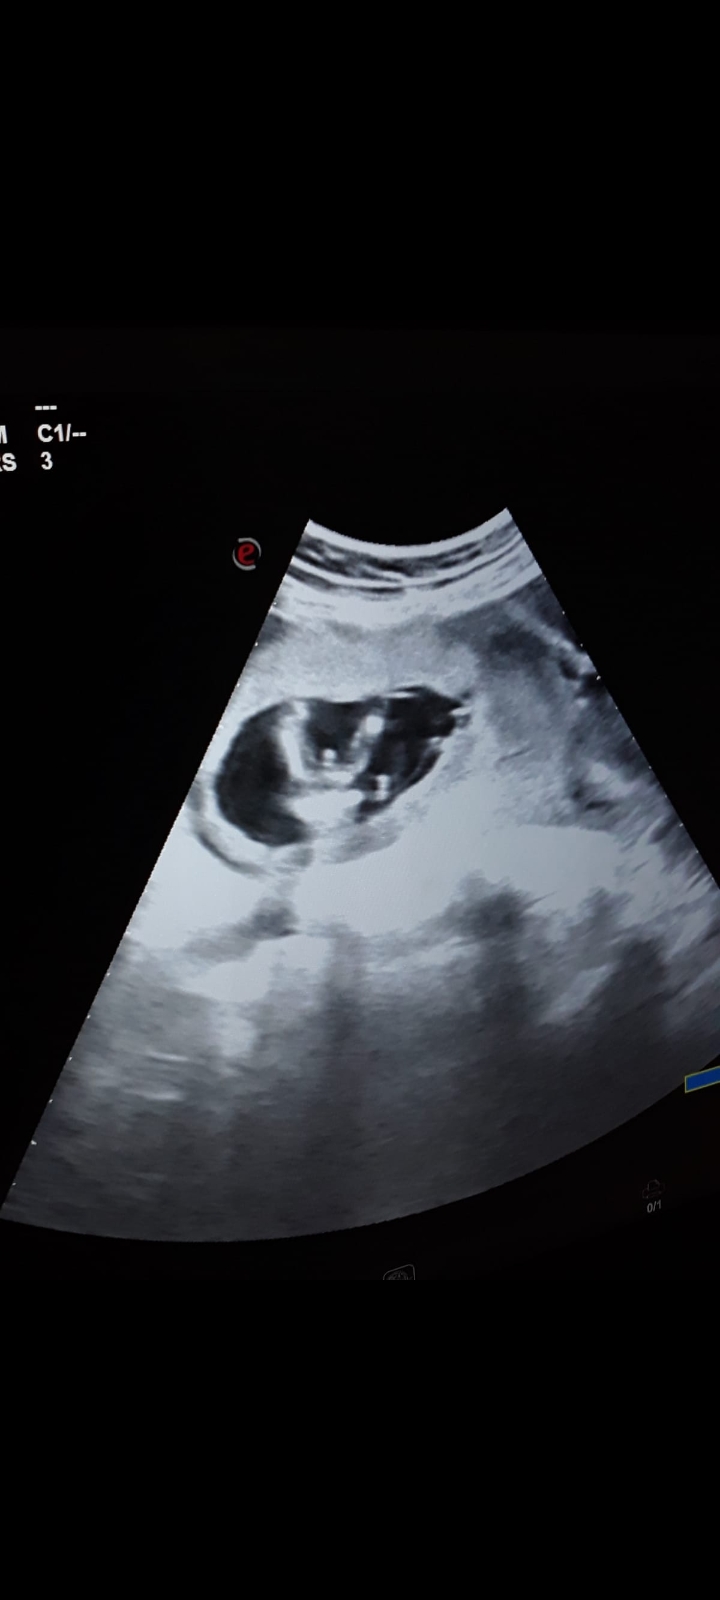

Cinsiyet icin yorum yapilan resim ekledim

Konu Başlığı Cinsiyet icin yorum yapilan resim ekledim

Benn bir ay oldu ogreneli ayrıntılı utrison öğrendim net bir ayın kaldi

Ozele gittim baştan oo doktor hiç birşey demedi bana cinsiyetini bile snra 7aylik oldum devlete gittim direk söyledi doktor bana ve her gittiğimde sykiyo bana consiyeti söyledim mi diye ve soyluyo